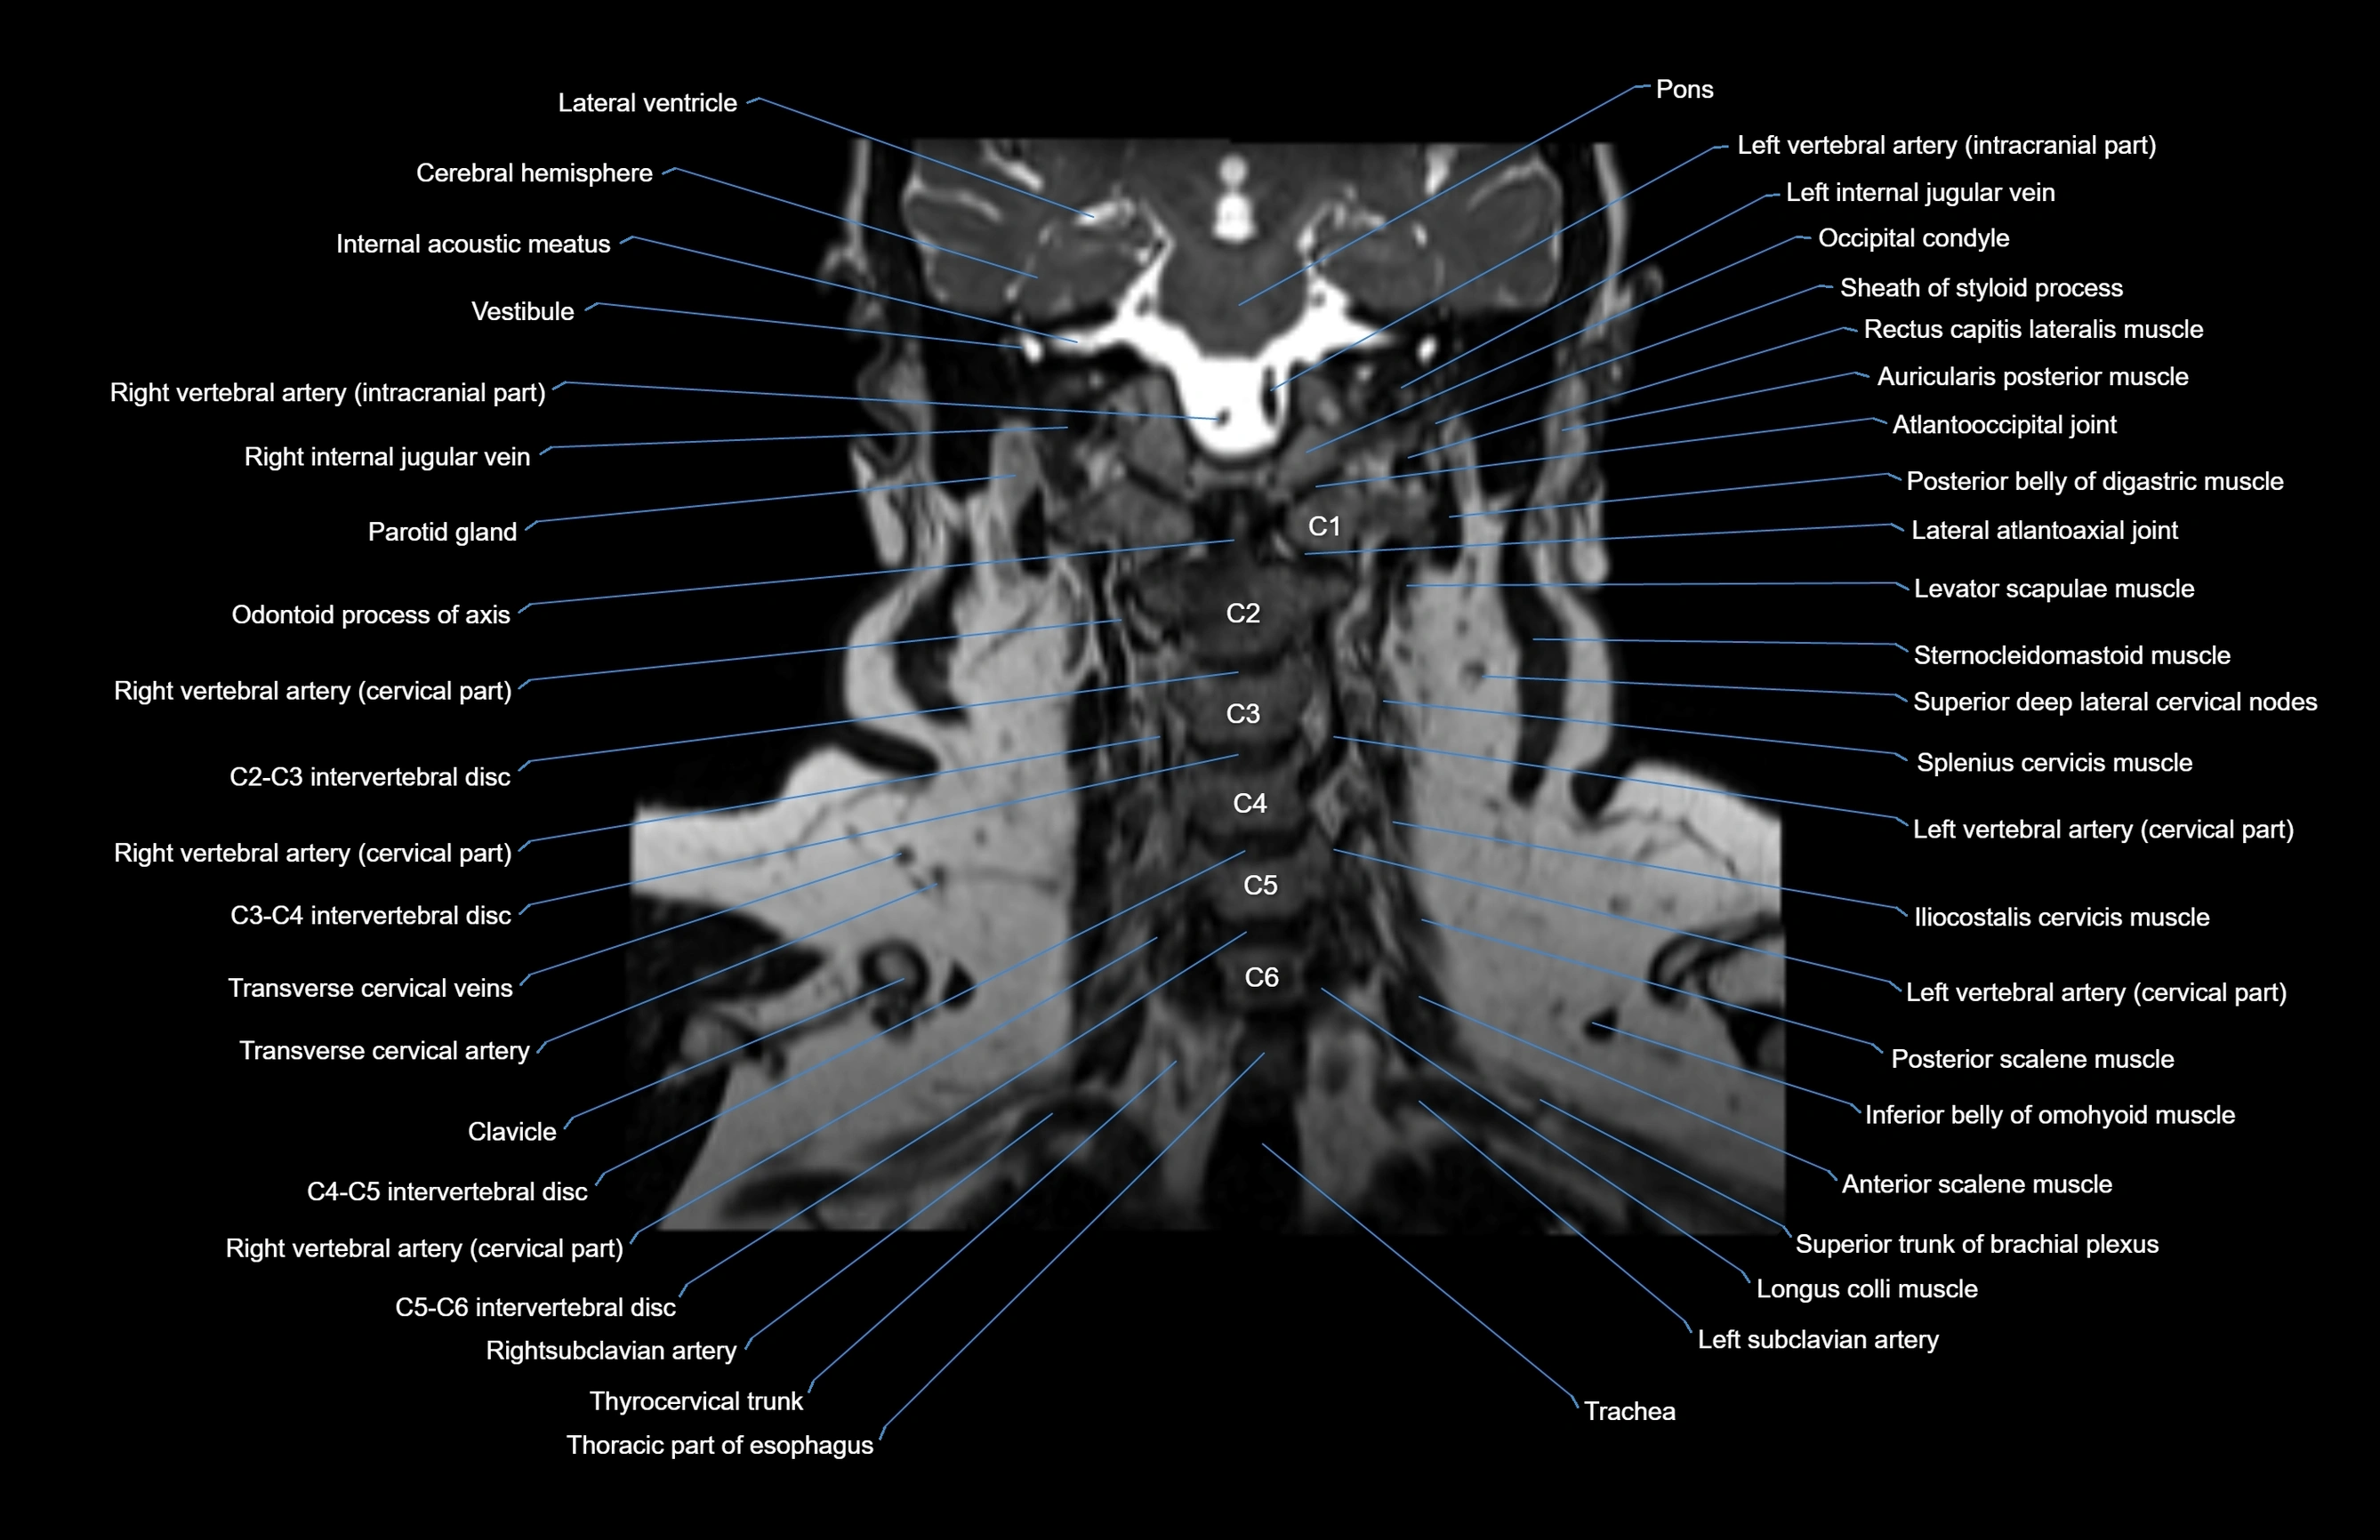

- Atlantooccipital joint

- Cervical spinal nerve 1 (C1)

- Cervical spinal nerve 2 (C2)

- Cervical spinal nerve 3 (C3)

- Cervical spinal nerve 4 (C4)

- Cervical spinal nerve 5 (C5)

- Cervical spinal nerve 6 (C6)

- Lateral atlantoaxial joint

- Left Vertebral Artery (Intracranial Part)

- Left vertebral artery (atlantic part)

- Left vertebral artery (cervical part)

- Occipital condyle

- Right Vertebral Artery (Intracranial Part)

- Right vertebral artery (cervical part)